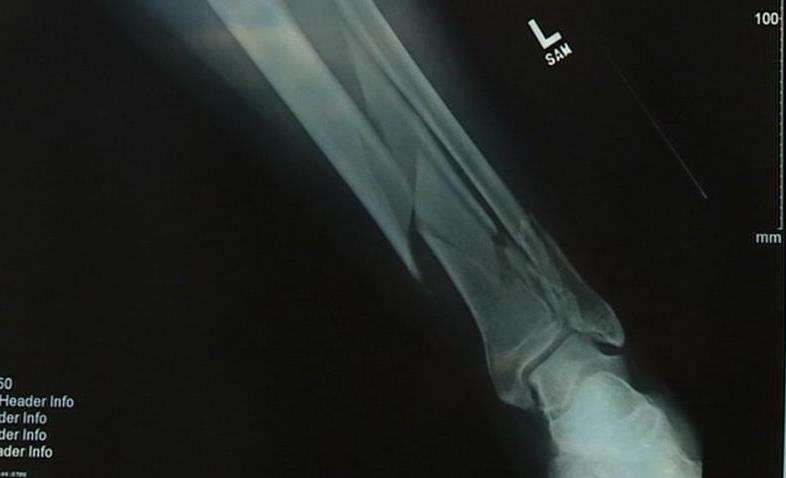

The infection stems from a broken leg that happened last September. Shurtleff was testing out a Harley-Davidson bike he planned to ride the next day, during the "Fall Ride for Fallen Officers."

Shurtleff broke his leg clean through in two places, but also shattered it in several locations. Surgeons put everything back together with rods and metal plates, but he's been in a lot of pain ever since.